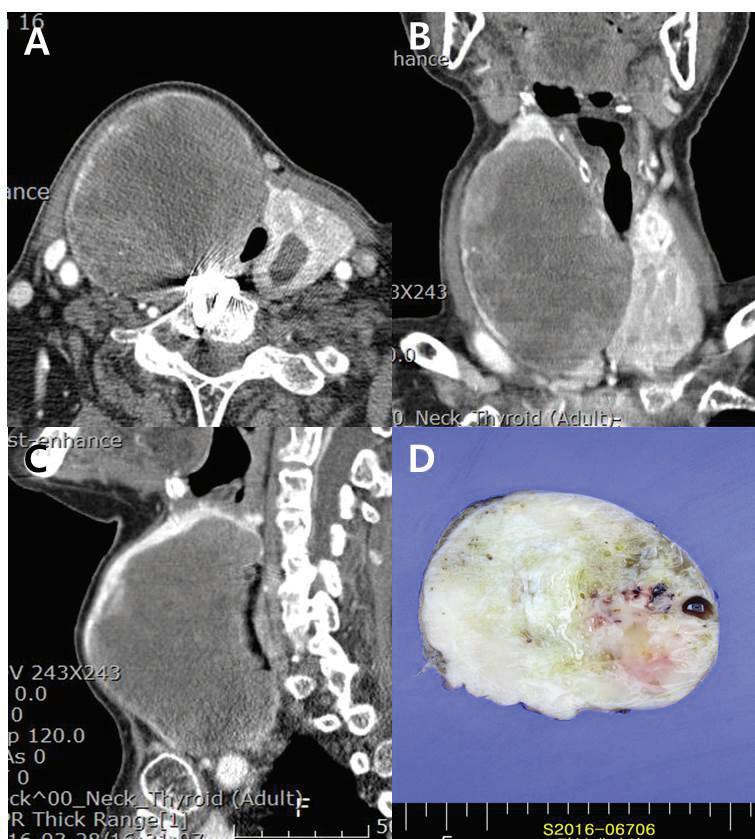

An 83-year-old woman who presented with aggravated dyspnea over a period of 1 month was admitted to our tertiary referral hospital. She had a history of Graves disease with a multinodular goiter involving the thyroid gland and had been receiving medical treatment with methimazole. On physical examination, a hard, protruding mass was noted in the anterior neck over the right thyroid cartilage. The cartilage was shifted toward the left side due to mass effect. Computed tomography (CT) with enhancement of the patient’s neck showed a huge (10 cm) mass in the right thyroid with luminal narrowing of the upper trachea due to mass effect (figure 1).

The patient underwent total thyroidectomy. Pathologic examination showed the mass to be positive for vimentin, cytokeratin, and actin, and negative for TTF-1, thyroglobulin, CD34, and EMA (figure 2). Therefore, the diagnosis of primary thyroid LMS was conclusive.

Considering the patient’s age and general condition, no other treatment was planned. At follow-up 12 months after surgery, the patient was still alive with no evidence of recurrence.

From the Department of Otolaryngology–Head and Neck Surgery, Research Institute for Clinical Medicine, Chonbuk National University, Chonbuk, Korea. Figure 1. A-C: Contrast-enhanced neck CT images show the 10-cm heterogeneous mass with rim calcification on the right thyroid gland. The trachea is deviated to the left. D: An excised surgical specimen shows a homogeneous and partially cystic change.